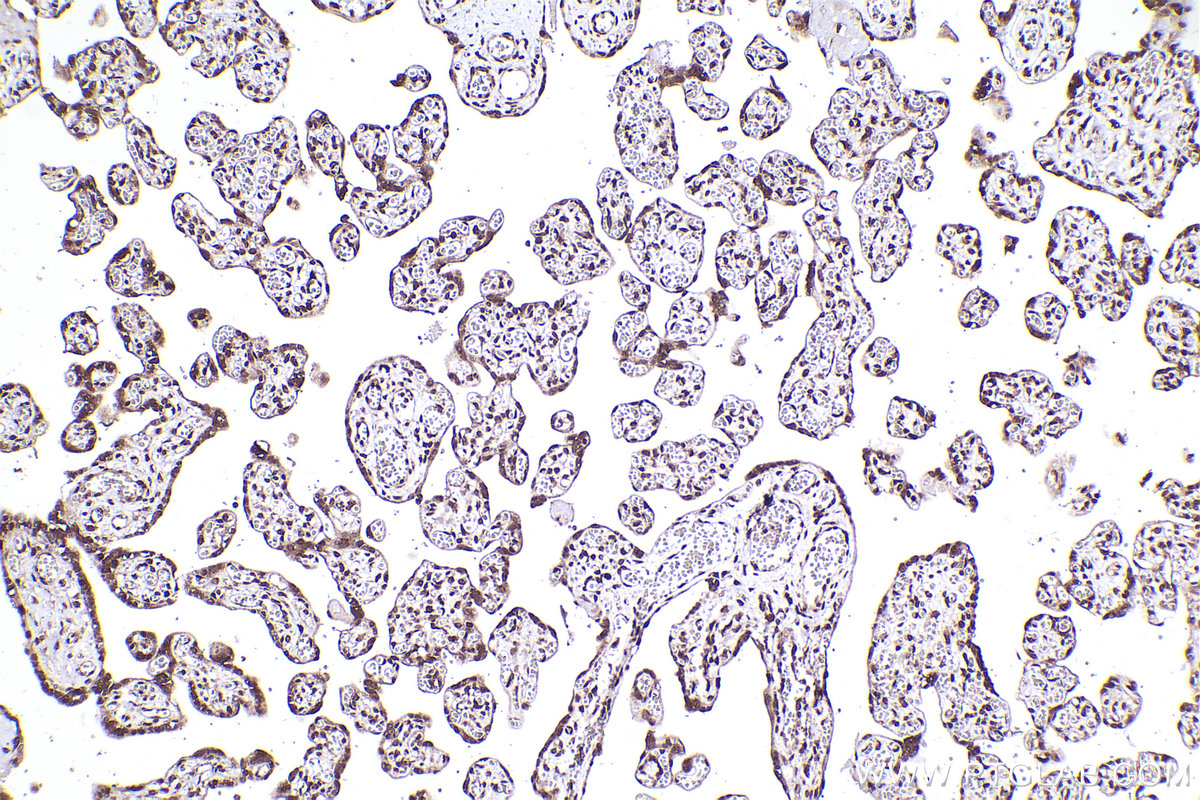

| Positive IHC detected in | human placenta tissue, human brain tissue, human heart tissue, human liver tissue, human ovary tissue, human skin tissue, human spleen tissue Note: suggested antigen retrieval with TE buffer pH 9.0; (*) Alternatively, antigen retrieval may be performed with citrate buffer pH 6.0 |

| Immunohistochemistry (IHC) | IHC : 1:500-1:2000 |